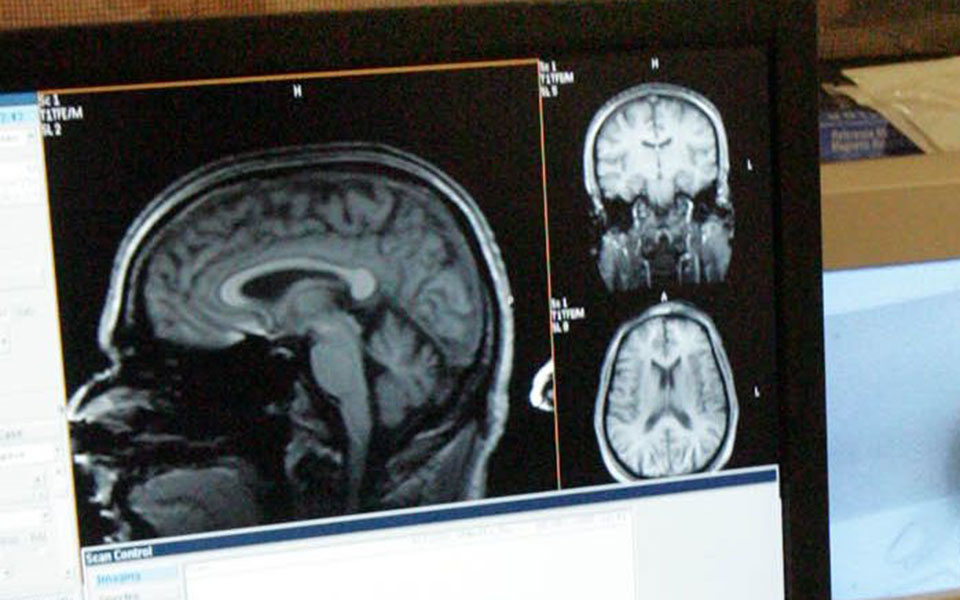

Η πρώτη, με επικεφαλής τον καθηγητή ακτινολογίας Χρήστο Νταβατζίκο της Ιατρικής Σχολής του Πανεπιστημίου της Πενσιλβάνια, αφορούσε 307 ασθενείς έως 45 ετών με σχιζοφρένεια και 364 υγιείς (ομάδα ελέγχου) σε τρεις χώρες (ΗΠΑ, Γερμανία, Κίνα). Παρουσιάστηκε στο περιοδικό νευροεπιστήμης "Brain" (Εγκέφαλος) και ανακάλυψε για πρώτη φορά ότι υπάρχουν δύο διαφορετικοί τύποι σχιζοφρένειας, διακριτοί μεταξύ τους από άποψη νευροανατομίας.

Η πρώτη έρευνα είναι η πρώτη που ανακαλύπτει διεθνώς ότι ο ένας τύπος σχιζοφρένειας, που είναι ο πιο συχνός, εμφανίζει μικρότερο όγκο φαιάς ουσίας στον εγκέφαλο σε σχέση με τους υγιείς ανθρώπους, ενώ ο δεύτερος τύπος (σχεδόν το 40% των ασθενών) έχει όγκο παρόμοιο με τον εγκέφαλο των υγιών. Η ανάλυση των απεικονιστικών εξετάσεων του εγκεφάλου όλων των ατόμων έγινε με τη βοήθεια του συστήματος τεχνητής νοημοσύνης "HYDRA", που ανέπτυξε η ομάδα του ελληνικής καταγωγής ακτινολόγου.